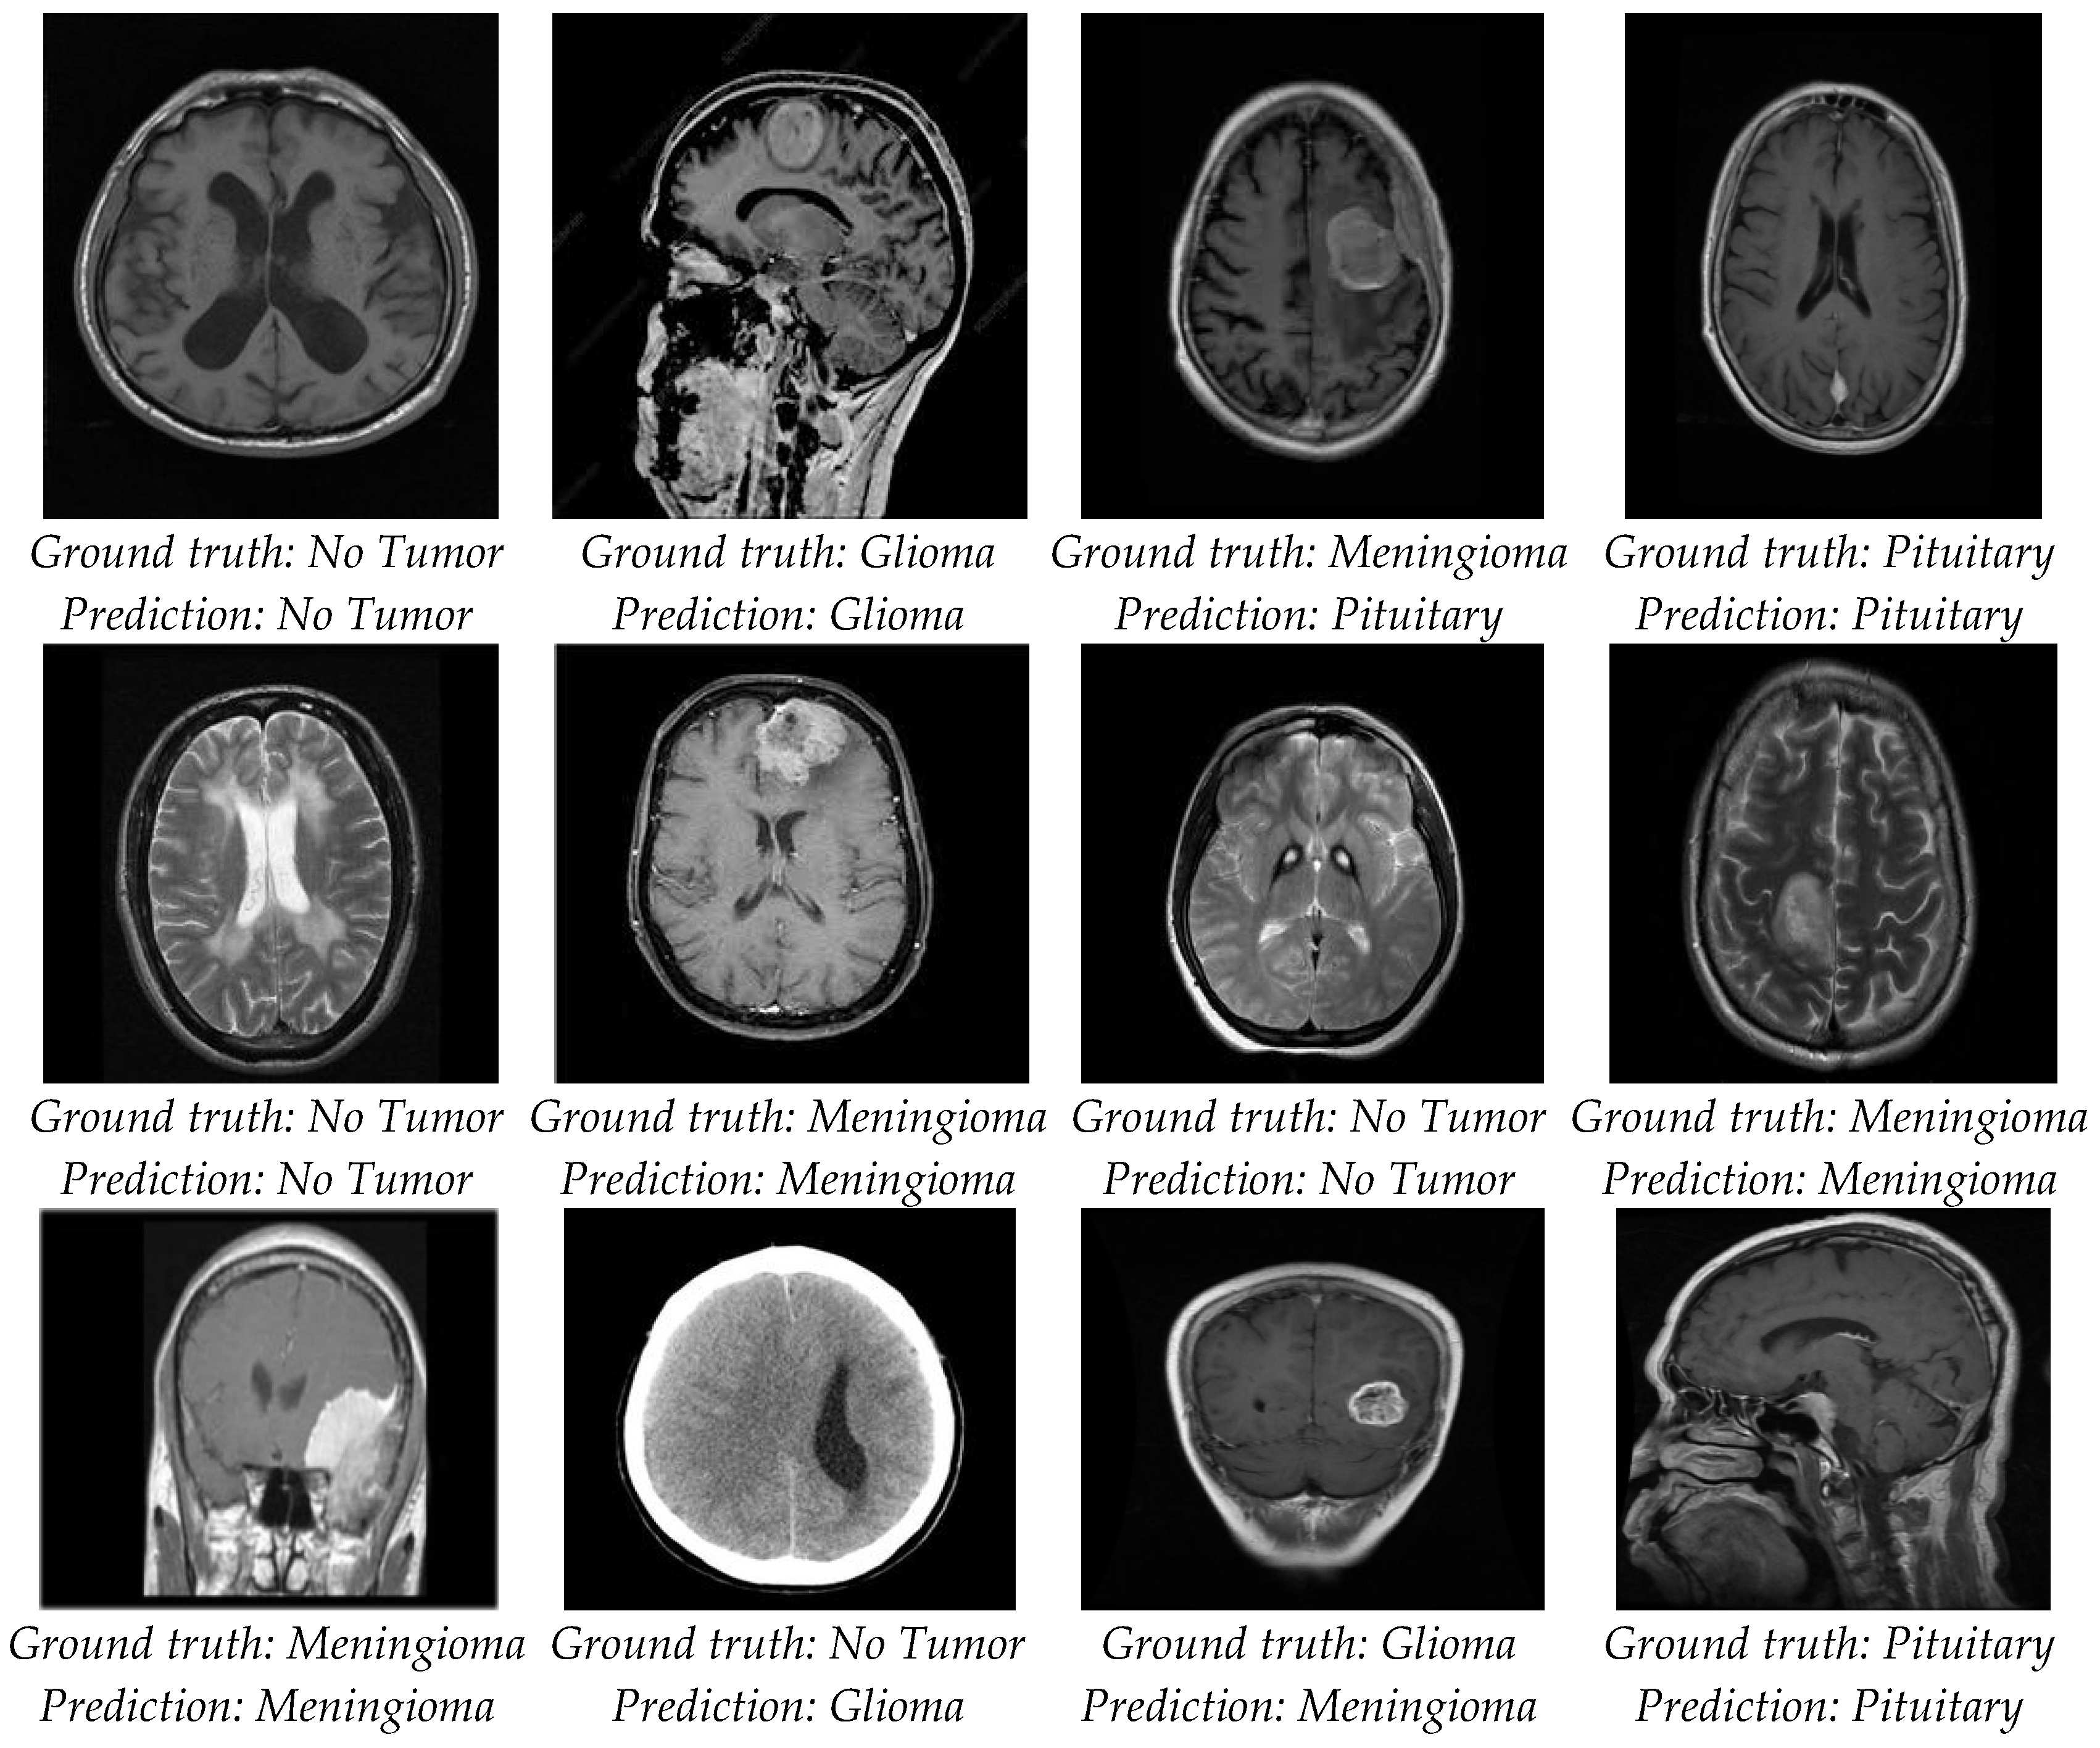

4.2. Classification Evaluation

5. Discussion

| Proposed | 98.56 | 99.14 | 99.25 | No Tumor |

| 98.24 | 98.66 | 99.19 | Glioma | |

| 98.50 | 99.14 | 99.10 | Meningioma | |

| 98.56 | 97.43 | 97.43 | Pituitary | |